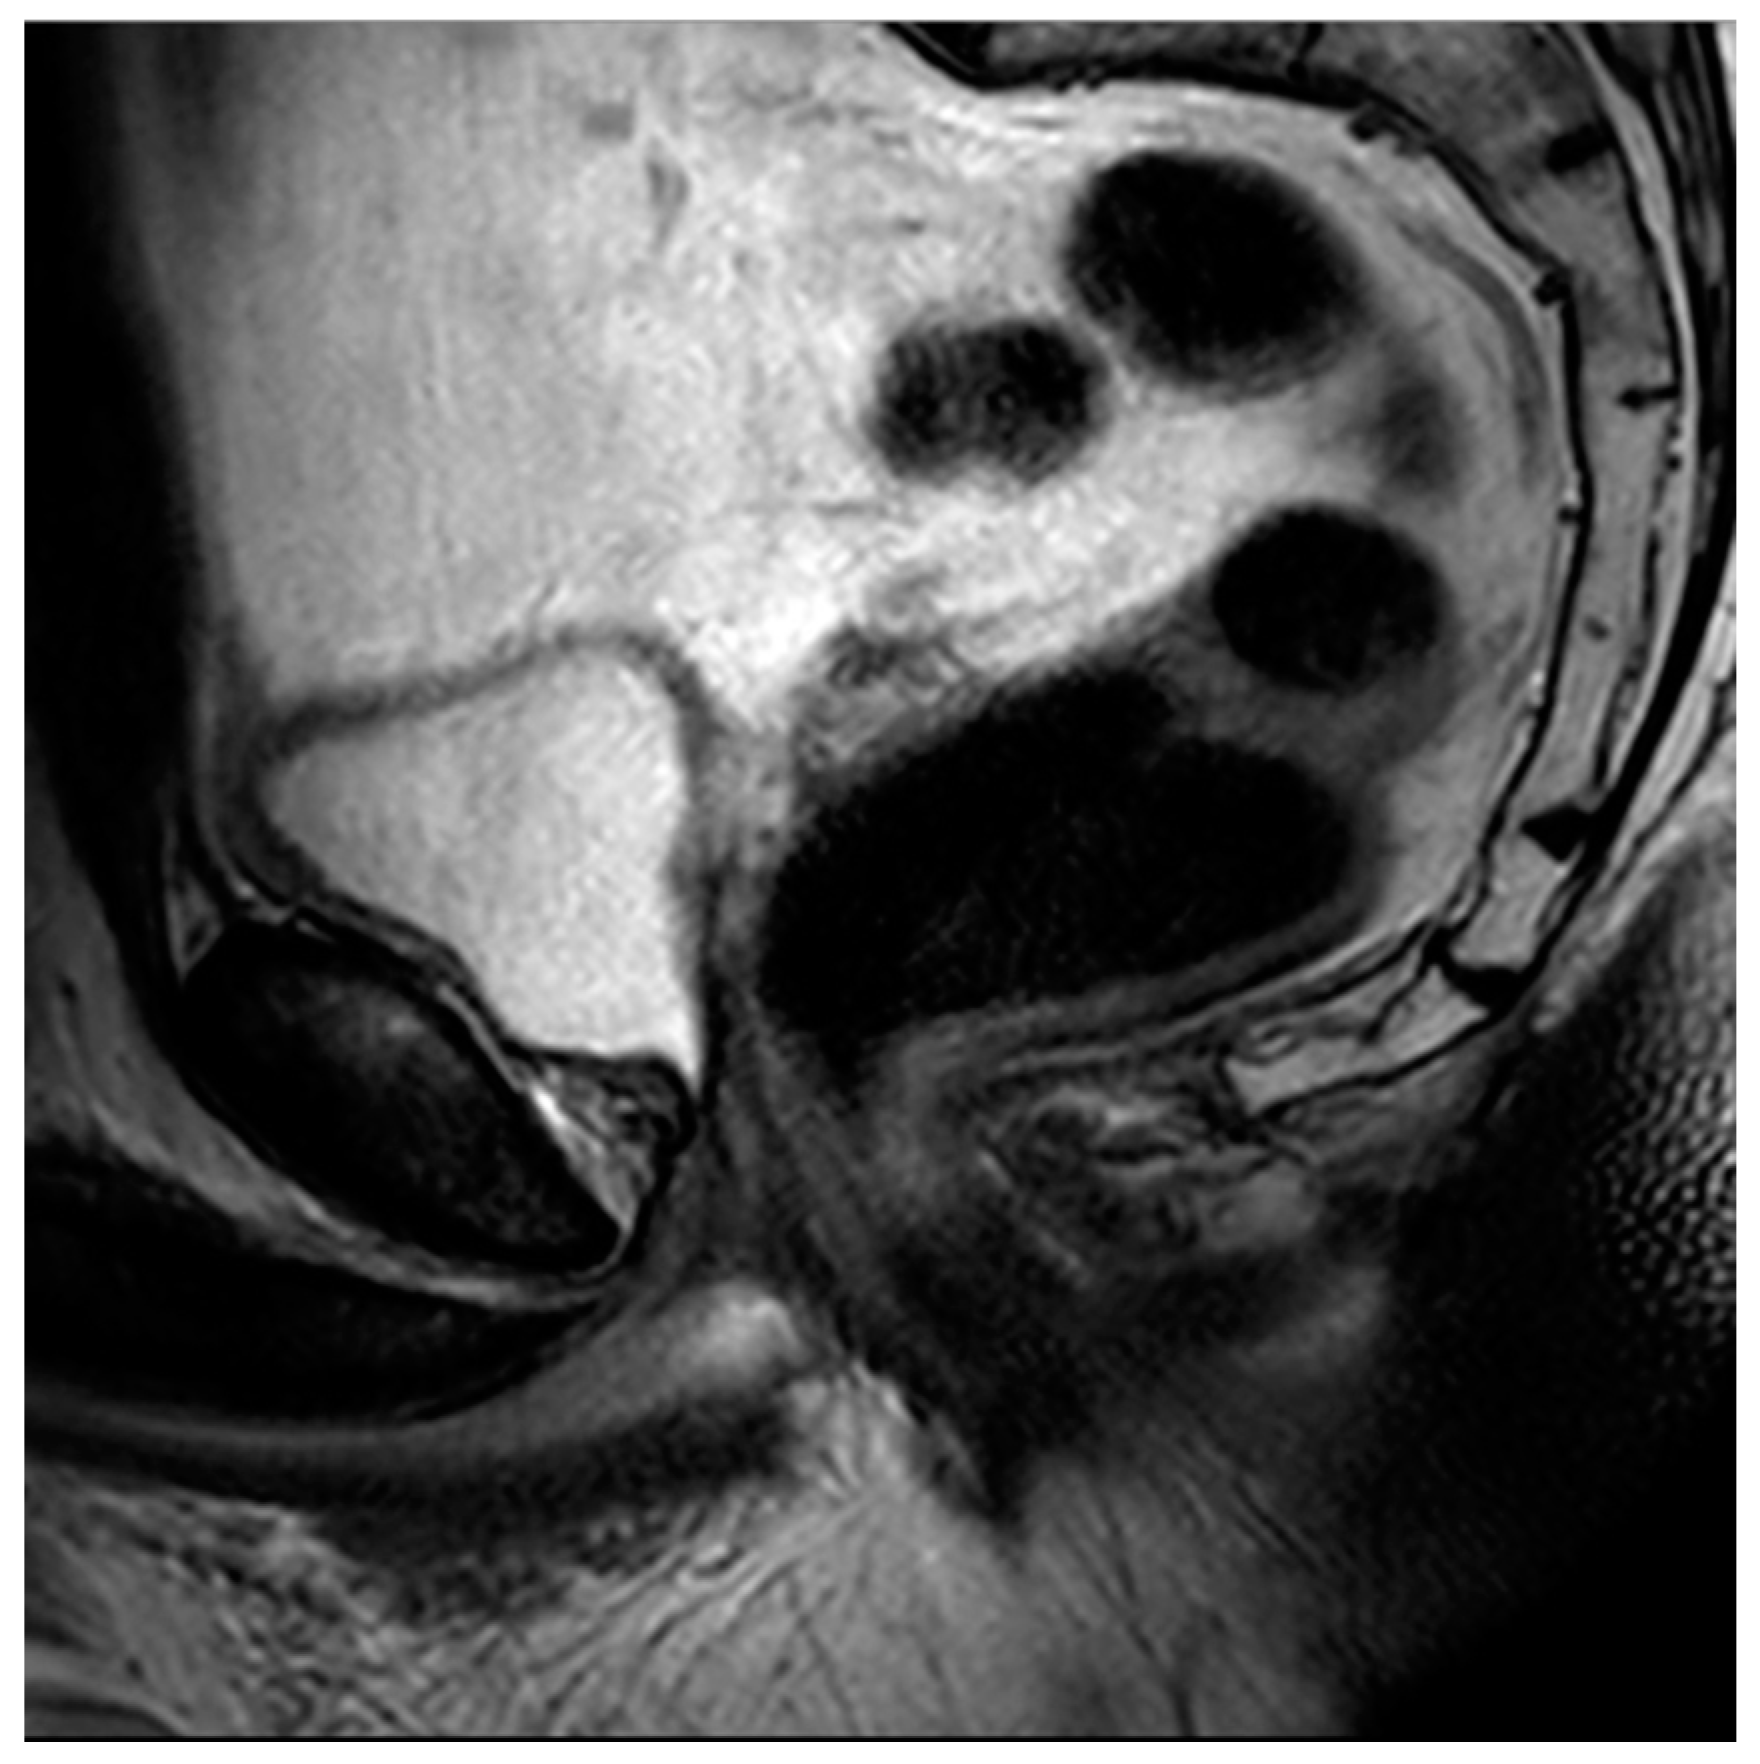

Figure 5. Sagittal T2 image demonstrating post-TURP changes of the prostate. Note the central defect at the level of the prostatic urethra and the relative absence of a median lobe.

The historical mainstay of surgical BPH is the transurethral resection of prostate tissue (TURP) [70]. This involves inserting a thin-loop wire electrode via a cystoscope and resecting adenomatous tissue in the prostatic transition zone that is responsible for bladder outlet obstruction (Figure 4). When using MRI, these changes typically present with an elongated, somewhat irregular appearance of the bladder neck and central prostate gland (Figure 5).

Laser enucleation of the prostate (LEP), commonly performed with either a holmium laser (HoLEP) or a thulium laser (ThuLEP), is an ever-increasingly used option for the treatment of BPH. These lasers were first used to vaporize tissue but are now more commonly used to enucleate the entirety of the gland, which is then mechanically morcellated within the bladder in order to facilitate expulsion. One major advantage of LEP, when compared to TURP, is that it is size-independent and can be implemented as a surgical option for glands of varying sizes [71]. When using MRI, LEP procedures look very similar to TURP but often have less residual peripheral tissue and a wider central periurethral defect (Figure 6). There can also be increased T2 intermediate signal and heterogeneity, which can impair the detection of prostate cancers.